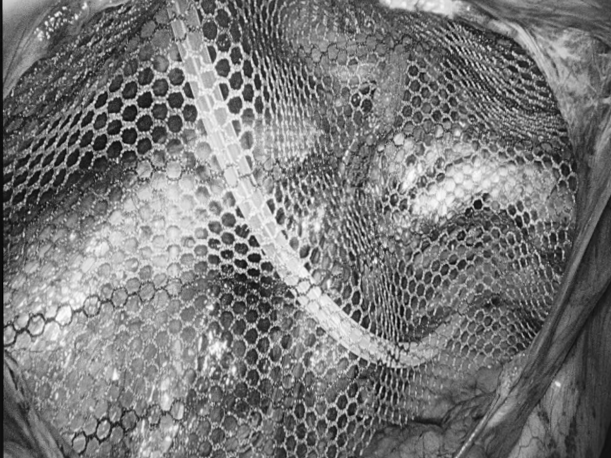

诊室里,经常能看到这样的画面:家长抱着哭得小脸通红、怎么哄都停不下来的宝宝,急急忙忙冲进来,“医生!快看看!孩子大腿根这里突然鼓了个包,越来越大!这可怎么办啊?!”——这种让人揪心的紧急情况,很多都是“小儿疝气”(俗称“小肠气”)惹的祸! 什么是小儿疝气? 简单说,就是宝宝肚子上有个“小洞洞”没长好(发病率为1%-4%),医学名称叫“腹股沟疝”,是小宝宝(尤其是男宝)很常见的一种情况。 为啥会这样?宝宝在妈妈肚子里时(先天性),腹股沟那里有个通道(学名叫“鞘状突”)本该自己关上的,但没关严实,就成了个“小洞洞”。当宝宝使劲哭闹、咳嗽、或者用力便便时,肚子里压力一大,一小段肠子或者组织就可能从这个“小洞洞”钻出,鼓起一个“包”。 最典型的表现:宝宝大腿根附近,出现一个“鼓包”,而且这个包在宝宝安静或躺平时,常常能自己缩回去(或者家长轻轻一推就能推回去)。 家长最关心的问题 1.必须要做手术吗? 在1岁以内有长好的可能,可以观察看看。超过1岁还没好,或者包块反复卡住(嵌顿)引起剧痛,千万别等了,尽早做手术,最佳手术年龄通常是1到3岁。 2.麻醉会不会伤脑子? 手术用的是全身麻醉,目前全球尚无研究证实规范全麻操作会影响智力或记忆力。宝宝就像睡了一个很沉很沉的觉,手术过程中完全没感觉、也不会记得。 为什么腹腔镜修补术比较适合宝宝? 传统开刀手术需在大腿根附近切开一个3厘米左右长的口子,手术后会留下挺明显的疤,恢复也慢。 腹腔镜修补术是通过肚子上3-5毫米(米粒般的大小)的小孔进行手术,同时能探查并处理对侧“隐性疝”,一次手术就搞定,不用再挨第二刀。术后一般6-8小时可以下床,24小时后能出院。 术前术后,家长这样配合更安心 术前准备 1.手术前6到8个小时别让孩子吃东西、喝水,防止打麻药时吐出来呛到。 2.按医生要求做抽血、凝血这些检查,看看孩子身体适不适合手术。 3.手术前一天给孩子洗个澡,把肚脐和大腿根附近洗干净。 4.多哄哄孩子,别让他哭得太厉害(哭狠了肚子里压力大,对手术不好)。 术后护理 饮食:术后6小时可少量喂水,无呕吐可逐渐恢复正常饮食。 活动:术后一周避免剧烈跑跳、哭闹或用力排便,防止腹压过高。 伤口护理:保持伤口清洁干燥,若发现红肿、渗液等不适,及时联系医生。 注:部分图片来源于网络,如有侵权,请联系删除。 贵州航天医院普外科专家简介 高大勇 普外科(肛肠外科)学科带头人、名誉主任,主任医师、教授 临床擅长:对中西医结合诊治肛肠学科各种常见病、多发病及疑难杂症等具有丰富的临床经验。 原遵义市第一人民医院(遵义医科大学第三附属医院)、遵义市中医院肛肠科主任。中华中医药学会肛肠分会常委,全国中医肛肠学科名专家,中国健康促进与教育协会肛肠分会常委,中国康复医学会肛肠疾病康复专业委员会常委,中国民间中医医药研究开发协会肛肠分会副秘书长,中国医师协会中西医结合肛肠医师专业委员会常委,国家二级心理咨询师,贵州省第一批中医名医工作指导老师,遵义市名中医,遵义市肛肠学会会长,遵义市肛肠质控中心名誉主任,遵义市中西医结合学会名誉会长,遵义市健康科普专家,原贵州省中西医结合学会肛肠分会副主任委员、贵州省中医肛肠质控中心副主任、遵义市医学会医疗鉴定委员会专家、遵义市卫生系列高评委。发表论文30余篇,主编和参编医学著作5本,主持省级科研课题2项、市级科研课题2项、院级科研课题1项。 梁 跃 中共党员,普外科党支部书记、主任,主任医师 临床擅长:对普外科各类肿瘤手术具有丰富的临床经验。 毕业于遵义医学院,遵义市医学会小儿外科学分会常务委员,遵义市肛肠协会理事,遵义市医学会核医学分会(第二届)委员会委员;荣获第三期“黔医人才计划”优秀学员称号;主持市级课题1项,完成省级课题1项,在国内各类刊物上发表论文10余篇。 钱科洪 民盟盟员,普外科副主任医师 临床擅长:从事普外科临床工作30余年,对各类普外科疾病的诊治、乳腺、甲状腺、胃十二指肠、结直肠等疾病及疑难杂症具有丰富的临床经验。 毕业于遵义医学院临床医疗系,2009年前往中山大学附属第一医院微创外科进修学习,在国内各专业期刊发表论文数篇。 贵州航天医院普外科简介 基本情况 贵州航天医院普外科成立于1968年,前身属于航天部O61基地3417医院外一科,1998年3417医院、3427医院合并后更名为普外科,下设胃肠外科、肛肠外科2个亚专业科室,拥有在全市较为先进的专科设备和技术,是中国疝病专科联盟单位,贵州医科大学附属医院胃肠外科专科联盟单位。开放床位40张,配备医护人员21人。 专科特色 普外科致力于胃肠及肛肠疾病的外科临床诊治及科研,以腹腔镜微创外科技术为本,形成以快速康复治疗胃肿瘤、结直肠肿瘤、小肠肿瘤、直肠脱垂、肥胖病、急腹症、各类疝、痔、瘘等专科特色,同时注重胃肠疾病尤其是结直肠恶性肿瘤的基础研究和临床转化研究,总体诊断和治疗水平在区域同级医院居于领先水平。 开展手术:腹腔镜下胃癌根治术,腹腔镜下袖状胃切除术,腹腔镜下胃肠道间质瘤切除术,腹腔镜下结、直肠癌根治术,胃癌、结直肠癌的精准治疗,腹腔镜下小儿疝气、成人疝修补术,腹腔镜下阑尾手术,内痔的硬化注射治疗及痔疮的微创治疗:ATH、PPH、TST,直肠脱垂的各种手术治疗,难治性伤口VSD技术,鼻胃肠管、肠梗阻导管置入术,肛肠术后间歇性导尿技术,并引进了中医适宜技术,也为各种化疗患者提供输液港安装,提高患者就医体验。 腹腔镜下腹股沟疝 无张力修补术 腹股沟疝里金斯坦(Lichtenstein)手术 PPH微创术治疗环状混合痔 黏连性或炎性肠梗阻-肠梗阻导管 腹腔镜袖状胃切除 腹腔镜阑尾切除术 腹腔镜阑尾肿瘤切除术 腹腔镜下结肠癌根治术 诊疗范围 胃肿瘤、结直肠肿瘤、小肠肿瘤、肥胖症、各类急腹症、腹部外伤、腹壁疝、便秘、直肠脱垂、痔疮、肛瘘、肛裂等胃肠、肛肠外科疾病。 END